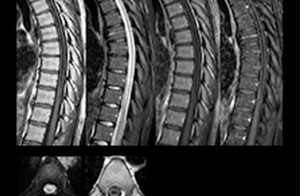

“We use mDIXON TSE extensively in our spine imaging in the emergency room,” says Dr. Karis. “It’s particularly nice in that it is very robust with regard to susceptibility type of problems that would come up with traditional spectral fat-saturated images; these problems are essentially eliminated with the mDIXON technique. In our ED environment it’s really nice to have the fat-free imaging that goes along with the mDIXON technique.

“For the thoracic and cervical spine routine non-contrast exam, for example, we perform one mDIXON T2 TSE sequence, which provides us with two outputs: the fat-and-water-together T2-weighted images, as well as the water-only sagittal T2-weighted images. And then we also perform an axial gradient echo exam.”

cervical spine mri in ed

Cervical spine routine exam

This patient presented with headache that was worse with neck flexion and we see a Chiari 1 malformation with low-lying cerebellar tonsils as well as some degenerative cervical thrombolytic change.